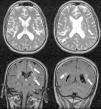

Encefalomielitis aguda diseminada tras infección por el virus de la gripe A (H1N1)

Acute disseminated encephalomyelitis after influenza A virus (H1N1) infection